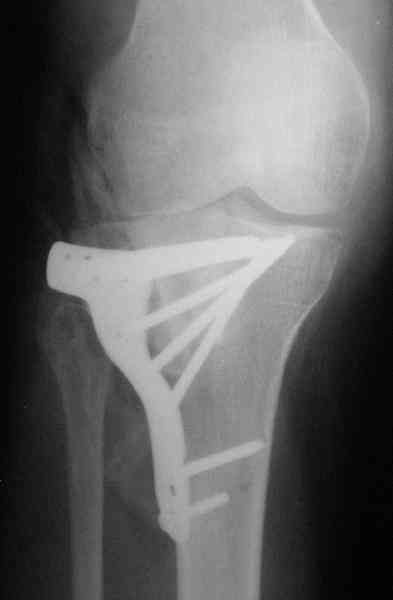

Уважаемый Абдурашид. Если нет противопоказаний , то из оперативных способов, я бы рекомендовал следующие: Полное замещение наружного мыщелка аллотрансплантатом либо открытая репозиция с элевацией и замещение дефекта ауто или аллокостью. В Ваших условиях , я бы рекомендовал второй способ. Во-время элевации необходимо разъединить фрагменты со стороны сустава ( надсечь скальпелем по линиям перелома, а затем тонким остеотомом их разъединить. При помощи долота произвести неполную остеотомию ( захватите не менее 1,5 - 2 см губчатой кости и поднять фрагменты, визуально отрепонировать и фиксировать 2-3 спицами. Дефект заместить костным ауто или аллатрансплантатом. Окончательная стабилизация пластиной ( лучше с угловой стабильностью, либо АВФ - позволит спокойно устранить угловую деформацию.

Недавно поступила больная через 1,5- 2 месяца.